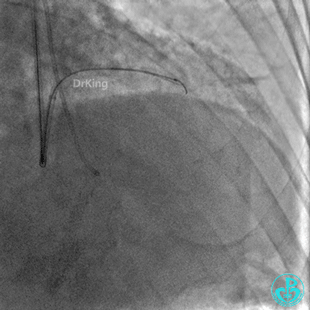

心包穿刺引流。

2根导丝进入到钝缘支分支远端,1根导丝送入微导管,另外1根导丝送入2.5×15mm球囊,2.5×15mm球囊远端Marker与微导管齐口(自制OTW球囊),经微导管缓慢推注明胶海绵糊。

钝缘支分支远端破口完全闭塞。